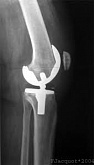

Еndoprosthesis of knee joint

In the late stages of arthrosis of the knee joint, accompanied by a pronounced restriction of the volume of movements, constant intense pain, deformity of the limb, the only way to recover is to replace the affected joint with an artificial joint - arthroplasty.

This method allows you to return the correct form of the limb, the full volume of movements in the joint, relieve the constant pain and crunch during movements and, as a result, significantly improve the patient's quality of life.

Below are presented X-ray photographs and photographs, illustrating the amount of motion in the affected joint before and after surgery.